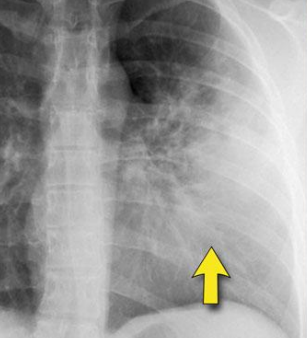

3

4

Menciona el patrón

Atelectasia